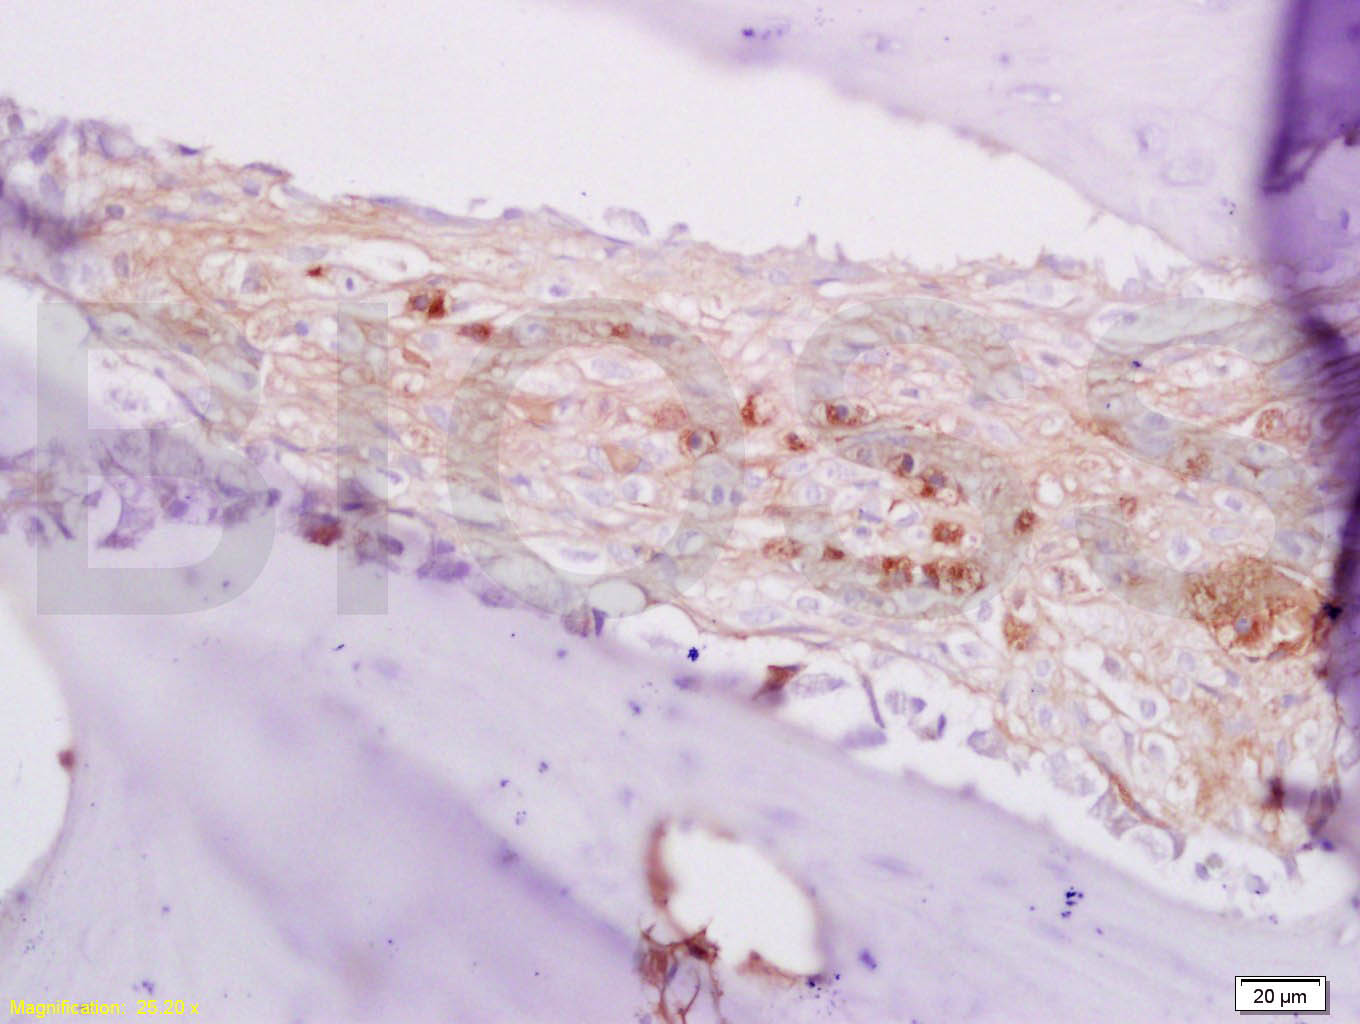

Tissue/cell: rabbit alveolar bone; 4% Paraformaldehyde-fixed and paraffin-embedded; Antigen retrieval: citrate buffer ( 0.01M, pH 6.0 ), Boiling bathing for 15min; Block endogenous peroxidase by 3% Hydrogen peroxide for 30min; Blocking buffer (normal goa